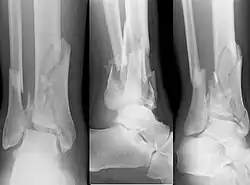

| X-ray of a fracture involving the articular surface of the Tibia | |

A pilon fracture, is a fracture of the distal part of the tibia, involving its articular surface at the ankle joint. Pilon fractures are caused by rotational or axial forces, mostly as a result of falls from a height or motor vehicle accidents. Pilon fractures are rare, comprising 3 to 10 percent of all fractures of the tibia and 1 percent of all lower extremity fractures, but they involve a large part of the weight-bearing surface of the tibia in the ankle joint. Because of this, they may be difficult to fixate and are historically associated with high rates of complications and poor outcome.[1][2][3][4]